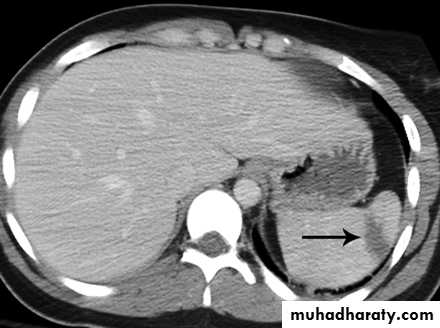

Spleen

CT

Splenic injurypancreas